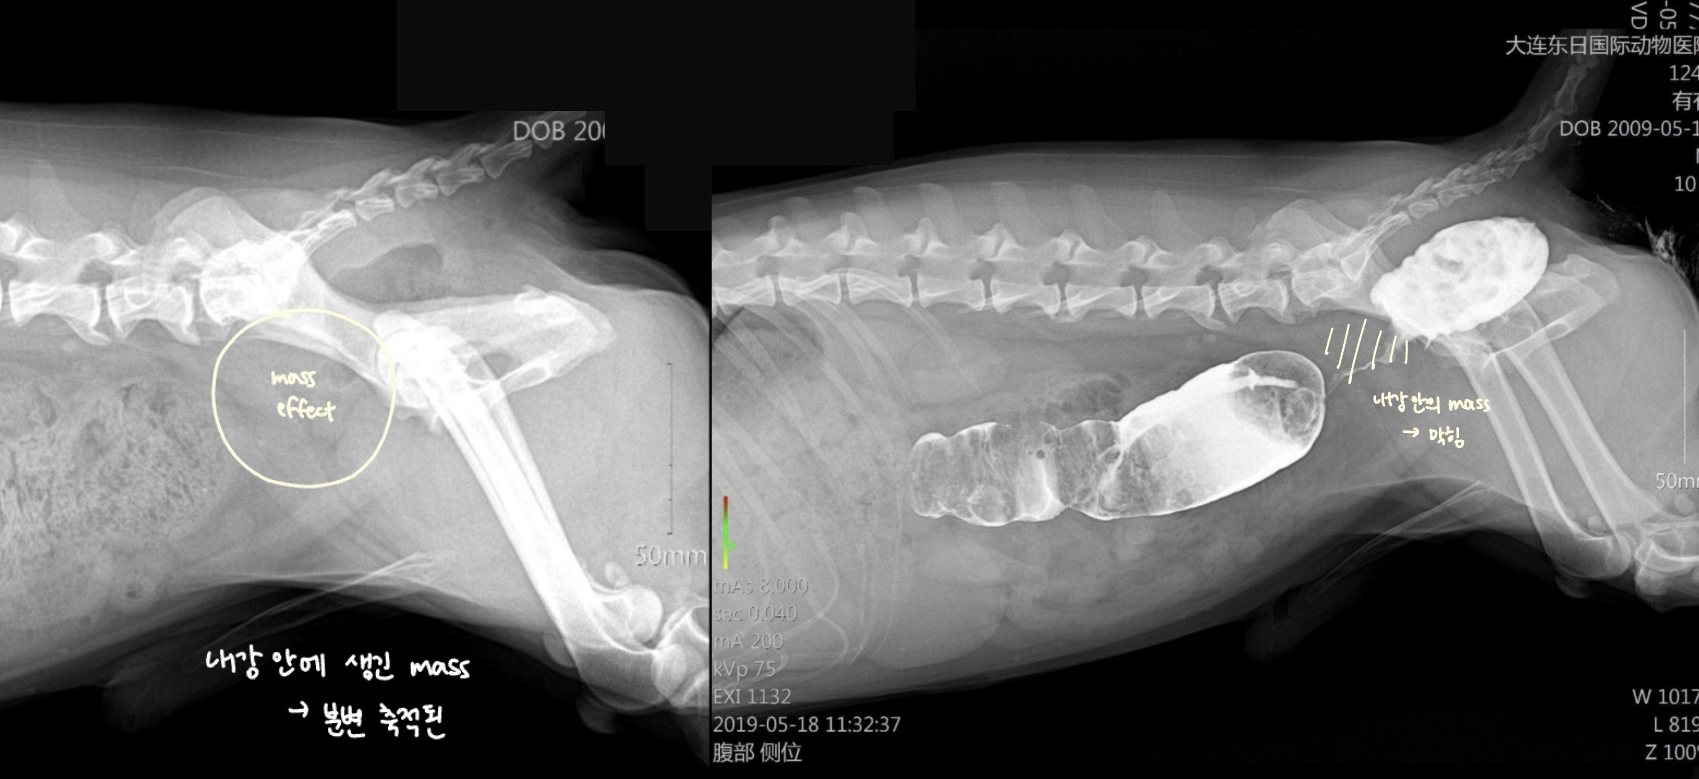

Intestinal tumor (์ฅ ์ข ์)

- ์ด์ง ์ ๋ฉ์ด๋ฆฌ๊ฐ ๋ง์ ธ์ง ์ ์์

- ๋ณต๊ฐ serosal detail ์ ํ

- ์๋ฒฝ, ์ฅ๋ฒฝ ๋นํ (์ ์๋ณด๋ค 2๋ฐฐ ์ด์ ์ฆ์ํ๋ฉด ์์ฌ)

- ์กฐ์ ์ ์ฅ๋ฒฝ ๊ฒฝ๊ณ๊ฐ ์ธํ๋ถํํจ (๋ด๊ฐ์ด ๊ฝ ์กฐ์ฌ์ ธ ์๊ธฐ ๋๋ฌธ)

- pseudoulcer sign (์ฃผ๋ณ ์ผ์ฆ์ผ๋ก ์ธํด ์ฅ์ด ์ญ๊ธํด์ ธ์ ์ฃผ๋ฆ ์ฌ์ด์ ์กฐ์์ ๊ฐ ๋จ์)

- ์ข ์์ ์ผ๋ฐ์ ์ผ๋ก ๊ทผ์ธต์์ ์์๋จ.

| Beak-shaped intestinal obstruction | DDx) |

|---|---|

| ๋์ฌ์์์ ์ฆ์์ด ๋ํ๋ ์ฅ๋ฒฝ์ด 360๋๋ก ๋นํ๋๋ฉด์ ์ ์ฒด์ ์ผ๋ก ์ข์์ง โ ์กฐ์์ ์ ์ฃผํ์ด ๋๊ฒจ ๋ถ๋ฆฌ์ฒ๋ผ ๋ํ๋๋ ๋ชจ์ ![]() ![]() | Intestinal mass 1. lymphoma 2. MCT |